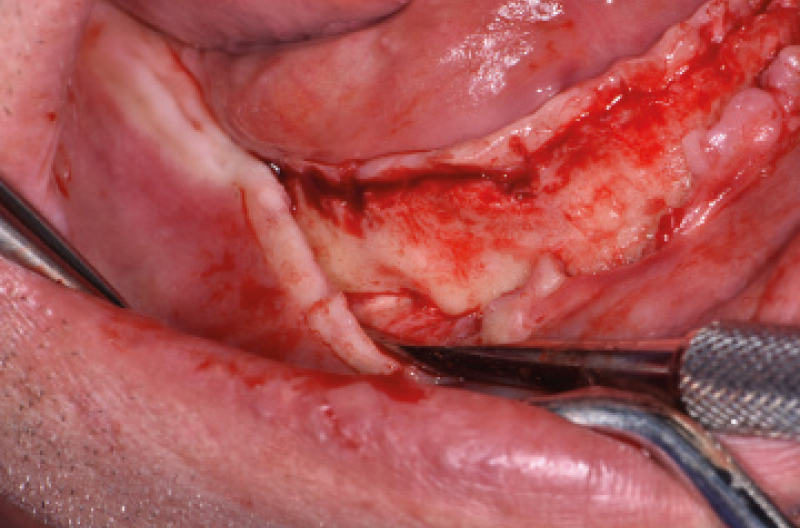

NellŌĆÖarcata inferiore ho posizionato distalmente 2 impianti Max Stability ├ś 3,75 mm L 12 e L 14 mm inclinati (ŌĆ£tiltatiŌĆØ) davanti ai forami mentonieri secondo il protocollo All-on-four, mentre nella zona sinfisaria ho inserito 2 impianti Narrow ├ś 2,9 L 12 mm (Figg. 15-20).

Fig. 16 – Esposizione del forame mentoniero di sinistra

Fig. 17 – Esposizione del forame mentoniero di destra